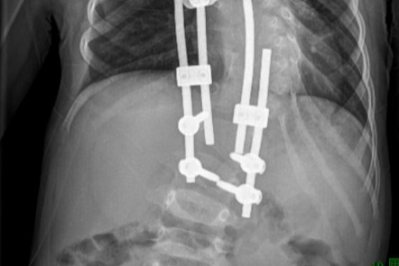

10 年矫治,武汉医生帮女孩拉直「乱成麻」的脊柱